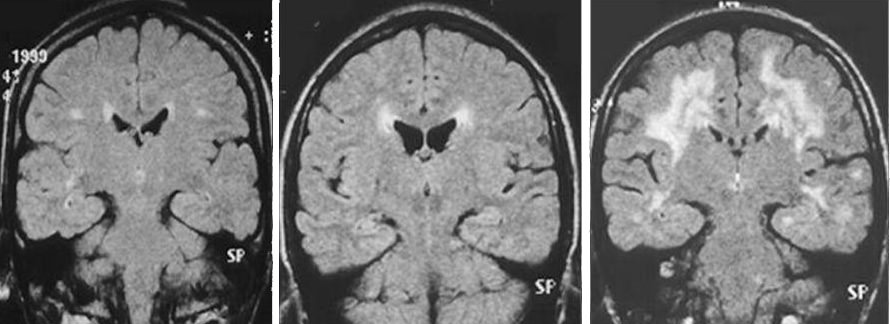

Изменения на МРТ сводятся к наличию очагов разрежения нервной ткани белого вещества (гиподенсивные зоны), расположенных вокруг желудочков или субкортикально, облаковидного лейкоареоза в виде локальных полей демиелинизации вокруг рогов боковых желудочков, в таламусе, стволе мозга, мозжечке. Часто появлению зон ишемии сопутствует расширение боковых желудочков и периваскулярных пространств. Наилучшую картину лейкоареоза можно получить при МРТ в режиме Т2-ВИ.

перивентрикулярный (слева) и субкортикальный (справа) лейкоареоз на снимках МРТ

Более информативна в постановке диагноза компьютерная или магнитно-резонансная томография. На МРТ снимках обнаруживают признаки измененного сигнала от белого вещества мозга. Такие очаги могут быть локальными или распространены по всему веществу мозга. Это свидетельствует о наличии ишемии. Стоит также отметить, что не всегда МРТ-картина соответствует состоянию больного. Часто при наличии множественных локусов лейкоареоза симптоматически заболевание практически не проявляется и наоборот.

примеры лейкоареоза различной выраженности у пожилых пациентов разного возраста (моложе → старше)